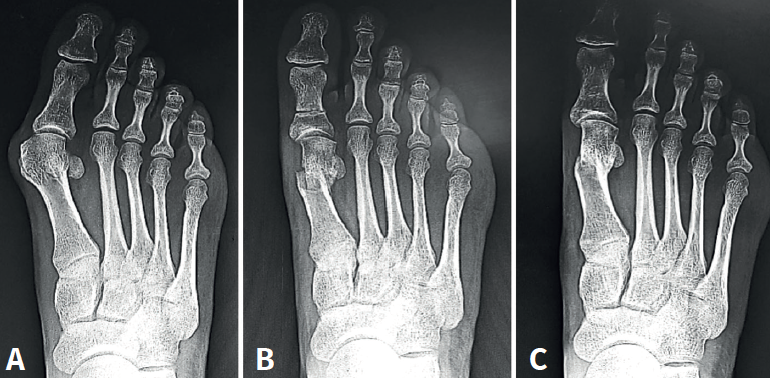

El HV° preoperatorio promedio (DE) fue de 32,67° (6,33). En el postoperatorio al año, el promedio (DE) del HV° fue de 11,51° (5,0), logrando una mejoría promedio del ángulo metatarsofalángico de 21,16° respecto al prequirúrgico.

El IM° preoperatorio promedio (DE) fue de 14,68° (3,26). En el postoperatorio al año, el promedio (DE) del IM° fue de 9,52° (2,58), logrando una disminución promedio de 5,16° respecto al prequirúrgico.

Con respecto a la elevación del metatarsiano, se obtuvo un promedio (DE) preoperatorio de 2,94 mm (0,92). En el postoperatorio al año el promedio (DE) fue de 3,97 mm (0,74). Se observó una diferencia promedio de 1,03 mm de elevación.

Los resultados angulares al mes y al año se reflejan en la Tabla 3.

Uno de los aspectos importantes en cuanto a la posición de la cabeza metatarsiana es el referente al plano sagital. Pocos trabajos de tratamiento de hallux valgus evalúan el ascenso de la cabeza. En este grupo de pacientes hemos observado que el ascenso de la cabeza es solo de 1,03 mm como promedio y no encontramos en la evolución alguna repercusión clínica asociada con dicho ascenso (Figura 5). Otro aspecto de la osteotomía en Chevron es que históricamente ha sido usada para la corrección de hallux valgus leves a moderados por su ubicación intraarticular, como es la forma clásica abierta o la moderna PeICO(11,12,13). Una de las modificaciones propuestas en este trabajo es hacer la osteotomía PECU a 7 o 10 mm proximal al centro geométrico de la cabeza (ubicación extraarticular), lo que nos permite un mayor desplazamiento y mejora el poder de corrección, asemejándose a una osteotomía diafisaria, como describen autores como Redfern, Vernois, Lee, Hernández, Bauer o Laffenétre en modelos de Chevron percutánea con fijación(3,4,5,9). En este trabajo fueron tratados hallux valgus graves (HV°> 40° e IM° > 16°) de forma satisfactoria.